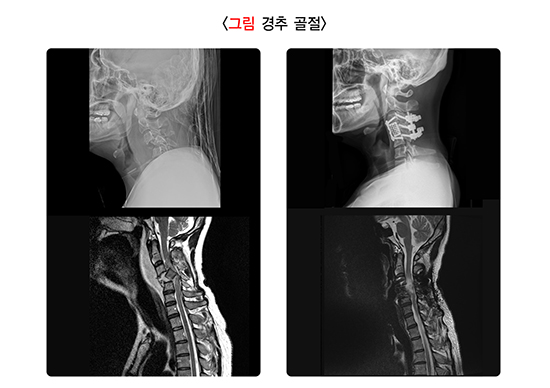

척추 손상의 가장 대표적인 형태로, 골절 및 탈구 등이 있습니다. 골절은 척추뼈가 외력에 의해 단절되거나 원래의 형태를 유지하지 못하고 변형된 경우를 의미하며, 탈구는 척추의 관절 부위 손상으로 인해 척추뼈가 제자리를 벗어난 것을 의미합니다. 골절과 탈구는 단독으로, 또는 복합적으로 발생할 수 있으며, 종종 관절 인대의 손상을 동반합니다. 골절 및 탈구의 경우 척추뼈에 힘이 어느 방향으로 가해졌는지에 따라 특징적인 형태를 보이며, 이런 외력이 작용한 방향에 따라서 골절 및 탈구를 분류하기도 합니다.

척추 손상이 의심되는 경우에 전통적으로 X-ray 검사가 일차적으로 사용되나 실제 골절 등을 발견하지 못하는 경우가 많아서, 골절이 의심되는 경우 뼈를 잘 볼 수 있는 컴퓨터단층촬영(Computed tomography, CT) 검사의 역할이 중요합니다. 다만 CT 검사로는 신경 및 인대 구조물을 잘 볼 수 없기 때문에, 신경학적인 문제가 있는 경우나 인대 손상에 대한 평가가 필요한 경우에는 자기공명영상(Magnetic resonance imaging, MRI) 검사도 같이 시행합니다.